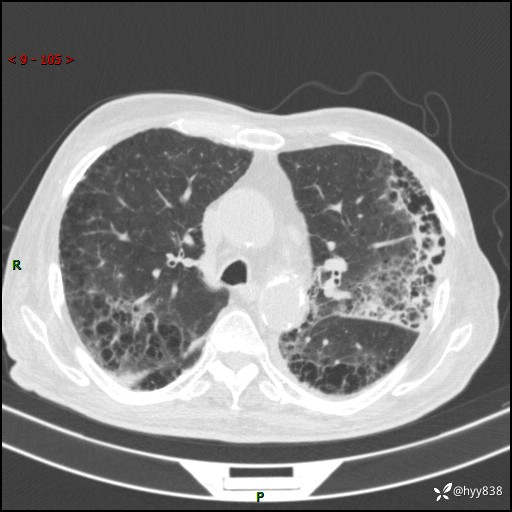

老年男性,间断咳嗽咳痰20余年,加重伴发热1天。呼吸科疑难病例讨论---结果公布

主诉:间断咳嗽咳痰20余年,加重伴发热1天

简要病史:家属代诉患者于20余年前无明显诱因出现咳嗽咳痰,痰为白色泡沫状,未行特殊治疗,不伴胸痛、胸闷、气喘、咳血等不适,1天前上午患者无明显出现发热,查体温39℃,伴咳嗽,咳痰无力,自行予以物理降温对症治疗,今晨2点左右再次出现发热,体温达40℃,自行服用复方氨酚烷胺对症治疗,凌晨3点左右复测体温38.2℃,现患者为求进一步诊治于今日就诊于我院门诊,行胸部CT提示双肺感染,遂以“肺部感染”收入我科。 患者本次起病来精神、食欲、睡眠欠佳,体力下降,体重无明显变化。

辅助检查:CT

胸部CT平扫